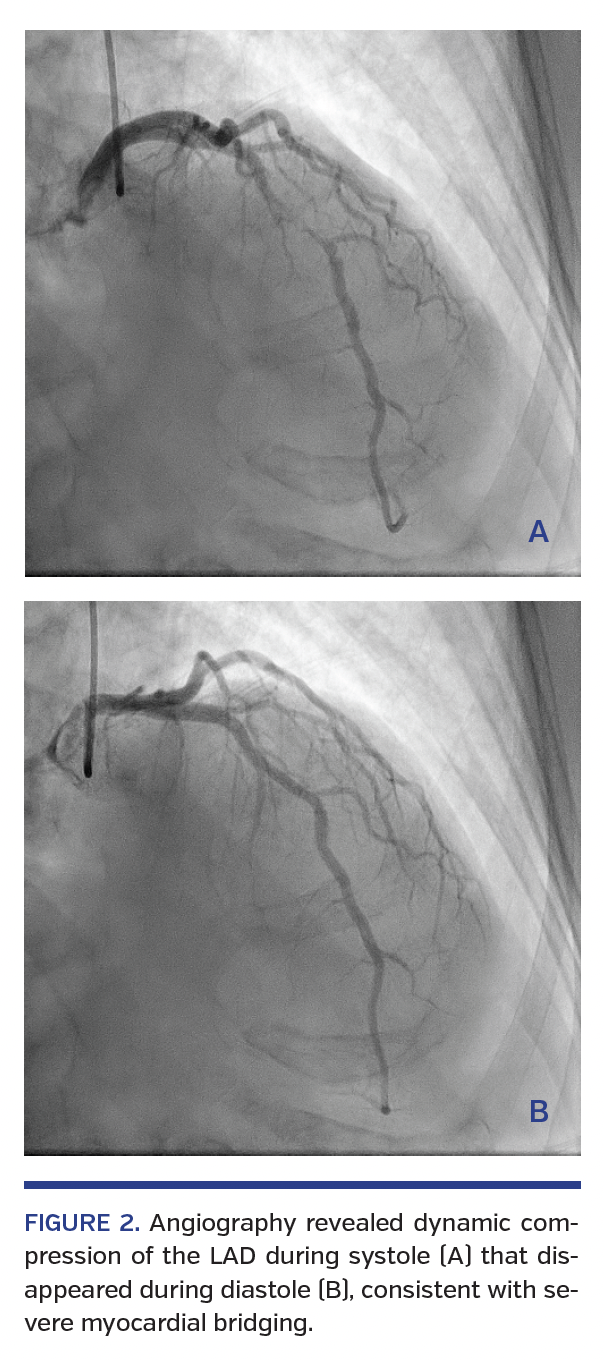

A 62-year-old woman with pancreatic cancer and no known risk factors for coronary artery disease was initiated on chemotherapy with home intravenous fluorouracil. Forty hours into the infusion, she presented with acute chest pain at rest. Initial ECG was unremarkable for ST-segment or T-wave changes. However, her chest pain intensified and repeat ECG showed ST elevations in I and aVL, hyperacute T waves in V3-V6, and ST depressions in V1 (Figure 1). She was taken emergently for coronary angiography, which revealed dynamic compression of the left anterior descending artery during systole that disappeared during diastole (Figure 2), consistent with severe myocardial bridging. There was no evidence of coronary atherosclerosis or vasospasm elsewhere. No coronary intervention was performed. Symptoms and ST elevations resolved with nitroglycerin. Cardiac biomarkers were undetectable and she remained asymptomatic. She was discharged on diltiazem and subsequently switched to a chemotherapy regimen consisting of gemcitabine and paclitaxel.